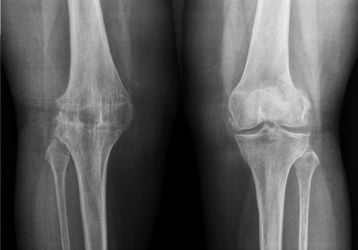

Чем отличается артрит от артроза коленного сустава: анализ признаков болезней

Методы диагностики и сравнение основных симптомов и признаков артрита и артроза коленного сустава, особенности обоих заболеваний.